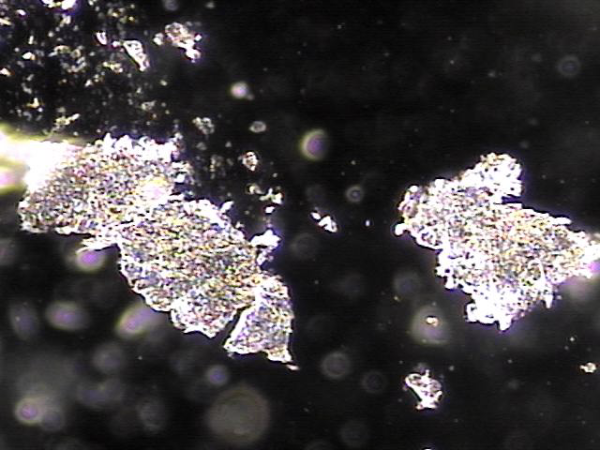

전립선과 정관의 표적 치료후 배출된 상피 세포 덩어리들(주2회 표적치료)

Epithelial cell clusters discharged after targeted treatment of the prostate and vas deferens (twice-weekly targeted treatment).

오랜 세월동안 탈락된 상피세포가 항문 주위에 결석을 형성하여 급박뇨와 야간 빈뇨를 일으키는 배출되지 못한 상피 세포가 전립선과 정관 그리고 사정관등에서 치료된 현미경학적 사진입니다.

This is a microscopic image showing the epithelial cell clusters that had built up over many years, forming small stones around the anal area. These blockages contributed to symptoms like urgency and frequent nighttime urination. With targeted treatment, these cells were successfully cleared from the prostate, vas deferens, and ejaculatory ducts.

주 2회 전립선과 정낭, 사정관과 정관등의 표적 치료후 막혀 있던 탈락된 상피 세포가 치료된 현미경학적 자료 입니다.

This is a microscopic image taken after twice-weekly targeted treatment of the prostate, seminal vesicles, ejaculatory ducts, and vas deferens. It shows that the shed epithelial cells that had been blocking these areas have been successfully cleared.